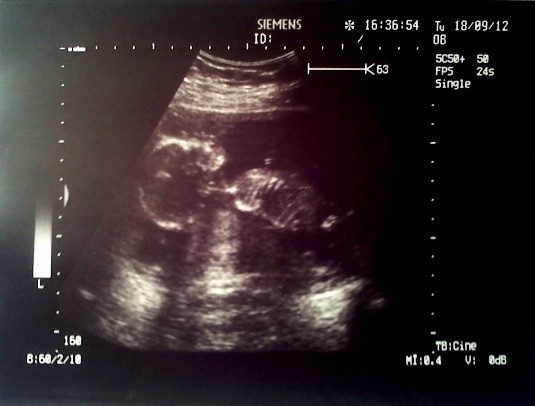

Aha i na tym pierwszym zdjęciu nie zostało uchwycone ale w tym momencie synuś "pukał" rączką w sufit. Jak to mój mąż stwierdził jak to widział na ekranie, że Robercik daje znać lekarzowi (cytuje) "idź mi z tym maziajstwem" miał na myśli głowice od USG, którą lekarz jeździł mi po brzuchu